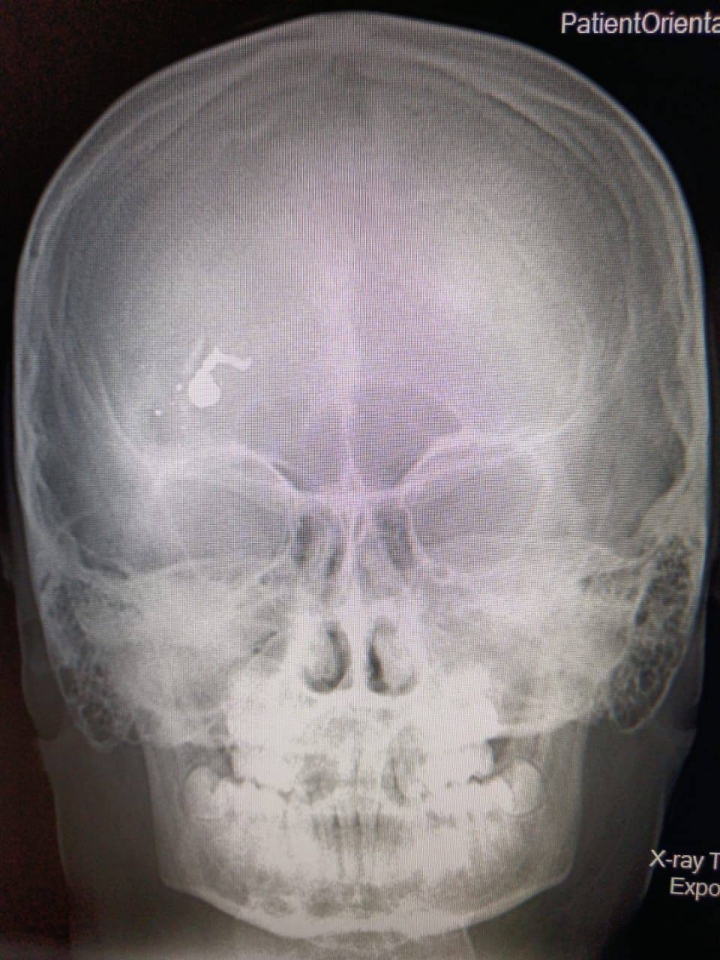

В Саратовской области произошел инцидент, в результате которого ребенок получил травму. На данный момент причины и обстоятельства произошедшего остаются неясными. Местные власти и правоохранительные органы проводят расследование, чтобы выяснить детали и причины данного происшествия.

По предварительным данным, инцидент произошел в одном из населенных пунктов региона. На место происшествия прибыли сотрудники полиции и медики, которые оказали первую помощь пострадавшему ребенку.

В настоящее время информация о состоянии здоровья ребенка не раскрыта. Ожидается, что власти дадут дополнительные комментарии по этому вопросу в ближайшие часы.